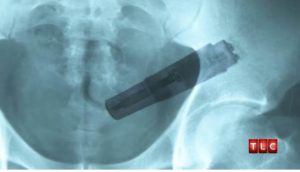

APUA! Hieromasauva lipsahti toooodella pitkälle!